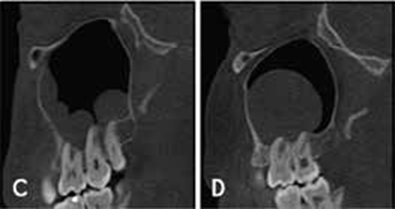

La physiopathologie des rhinosinusites repose sur l’œdème de la muqueuse qui au début est le résultat d’une implication multifac- torielle : l’inflammation – l’infection virale ou bactérienne – l’al- lergie nasosinusienne – la pollution de l’environnement – le taba- gisme actif surtout mais passif également. Cet œdème entraine un blocage et une obstruction des ostiums sinusiens (orifices de drainage). Ceblocage anatomo-fonctionnel entraîne une hypoxie muqueuse qui génère à sontour un œdème contribuant ainsi à la pérennisation de l’œdème de la muqueuse rhinosinusienne.

Un investissement en locaux se traduit tout d’abord par une architecture appropriée, devant rassembler plusieurs locaux contigus [3] (Figure 1), notamment :